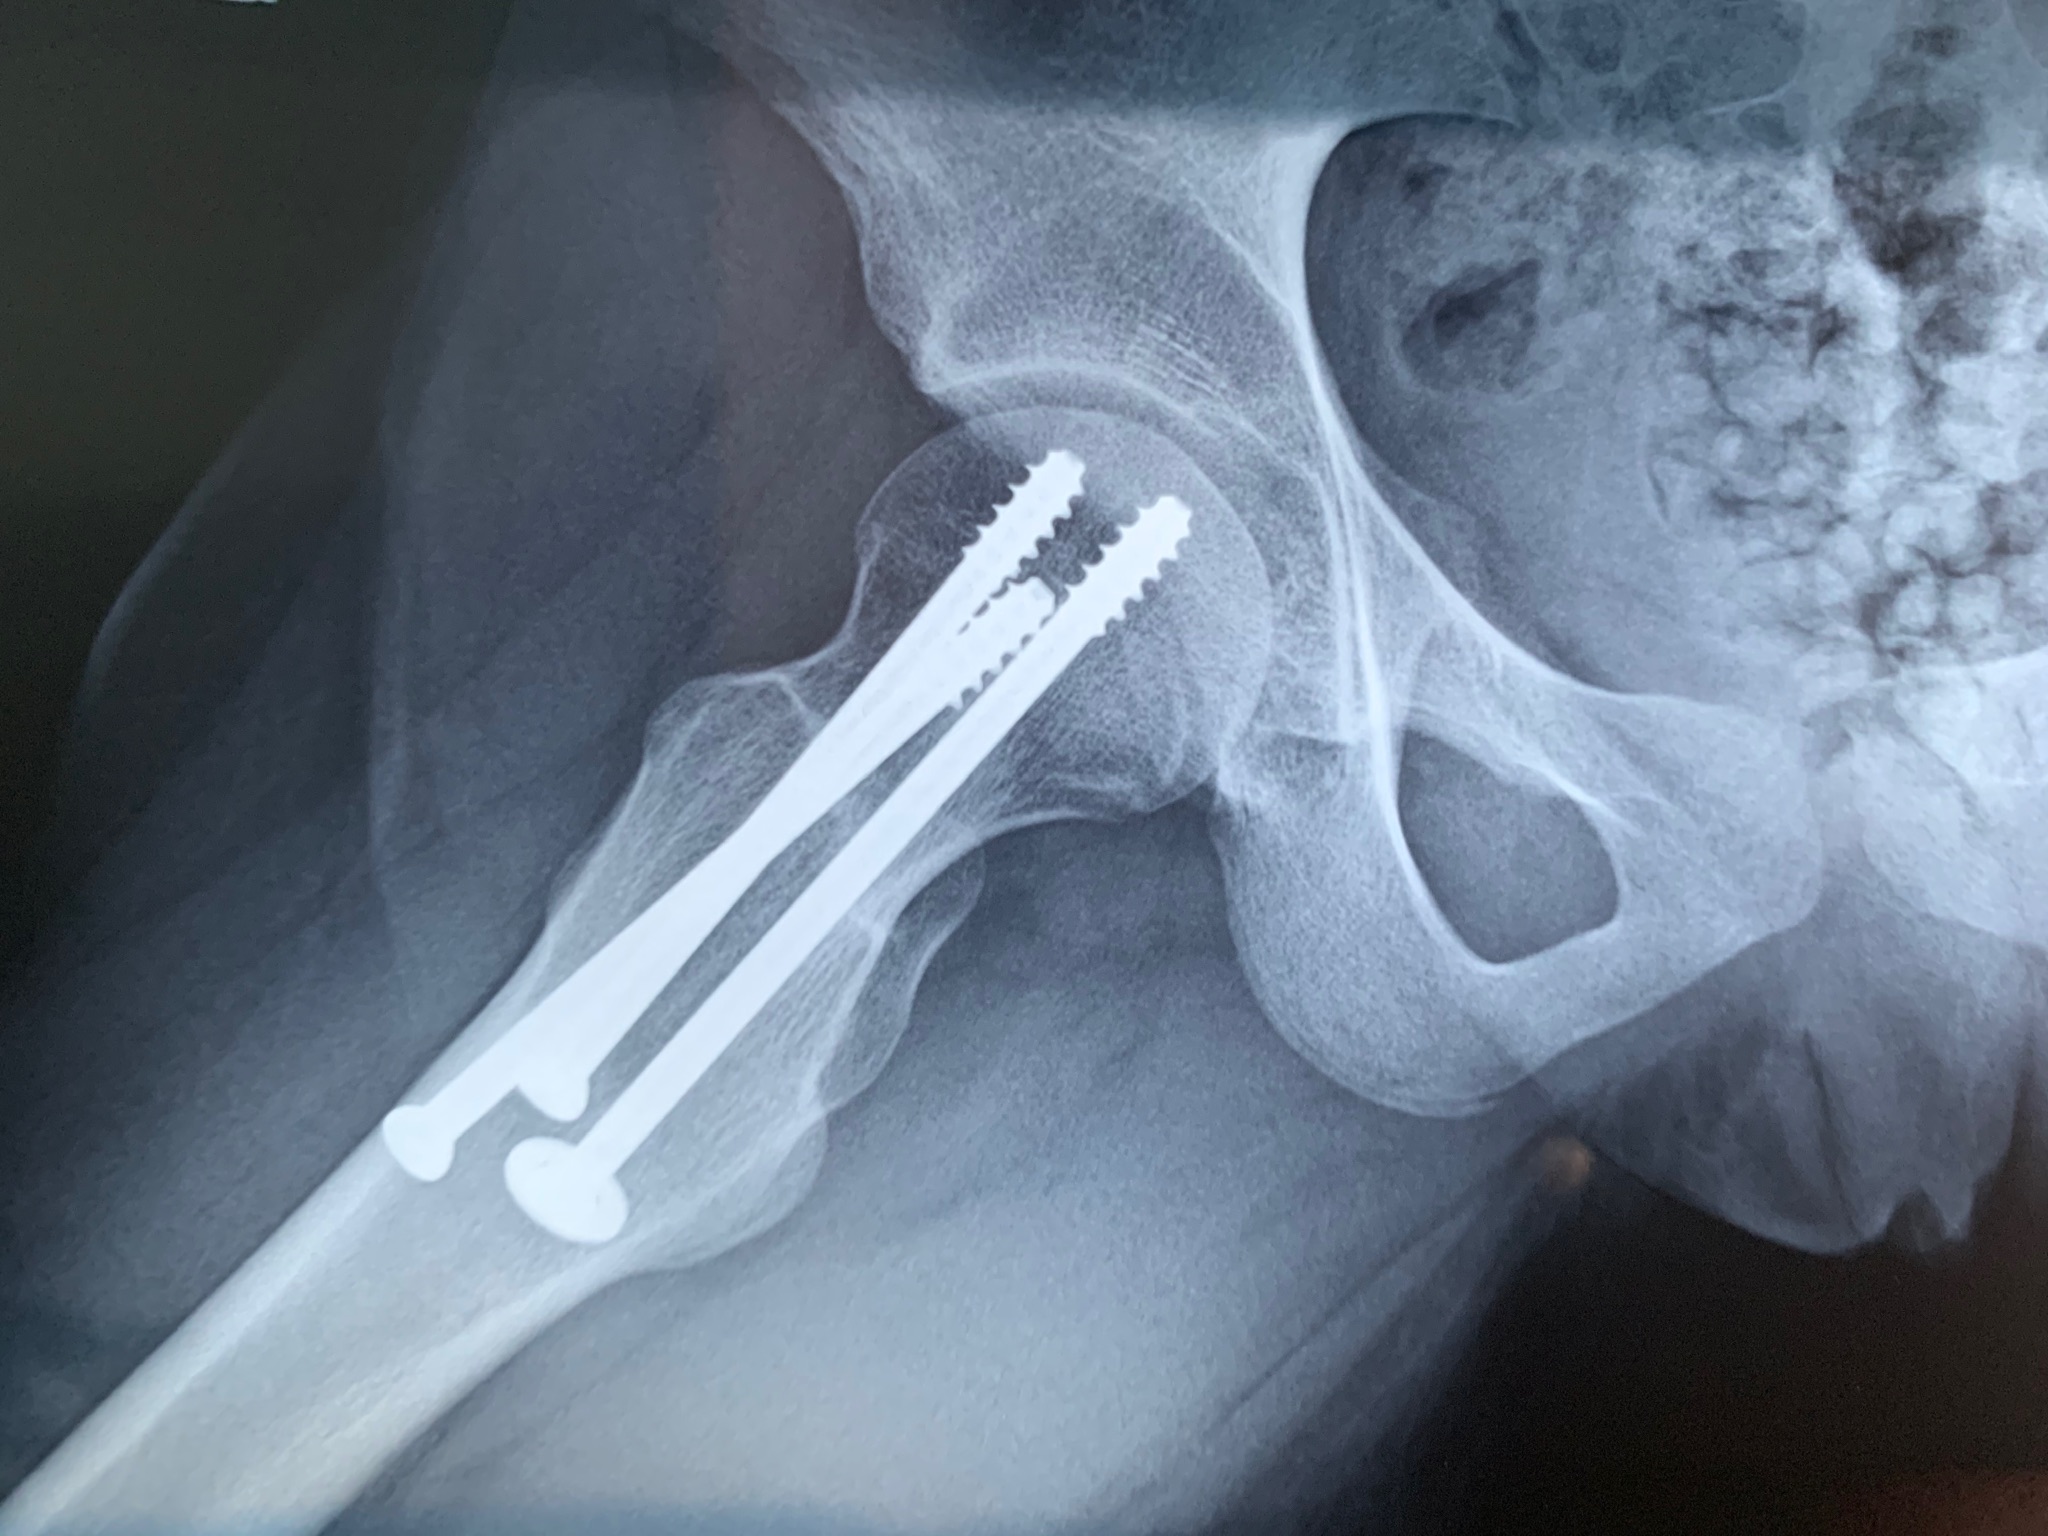

Mia figlia, oggi quattordicenne , un anno fa cadendo ha rotto il collo del femore.È stata operata immediatamente e le sono state inserite 3 viti. È ormai passato un anno e abbiamo eseguito i controlli di routine.

Il collo del femore fratturato è guarito perfettamente, non si parla di rimozioni delle viti di sintesi, mi chiedo se invece, considerando consolidata la frattura, perché conservare 3 viti, all’interno dell’osso se effettivamente non servono e anche se un domani succedesse qualcosa ci sarebbero sempre le tre viti...

2D348DFA-9A97-4CB7-9B43-5FAAA628904D.jpeg

[ 477.12 KiB | Osservato 1100 volte ]